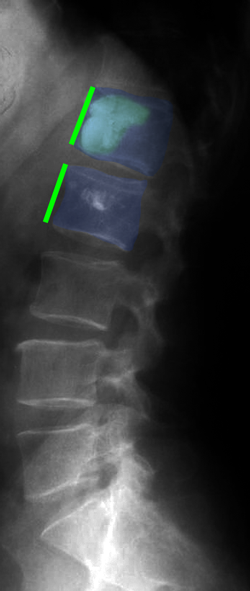

Διαδερμική κυφοπλαστική, ακτινοσκόπηση. Η ειδική βελόνη εισέρχεται διαδερμικά στο σώμα του σπονδύλου (φούξια βέλος) και γίνεται έκπτυξη μπαλονιού το οποίο ανατάσει το οστεοπορωτικό κάταγμα (αριστερά). Κατόπιν πραγματοποιείται έγχυση ακρυλικού πολυμερούς στο σώμα του σπονδύλου για να σταθεροποιηθεί το αναταχθέν κάταγμα (δεξιά). |

Κάταγμα 01 (φούξια) με μείωση του ύψους του σπονδύλου σε σύγκριση με τον υποκείμενο υγιή σπόνδυλο (μπλέ)(αριστερά). Κυφοπλαστική με ανάταξη του κατάγματος και επαναφορά του ύψους του σπονδύλου στο φυσιολογικό (δεξιά). |